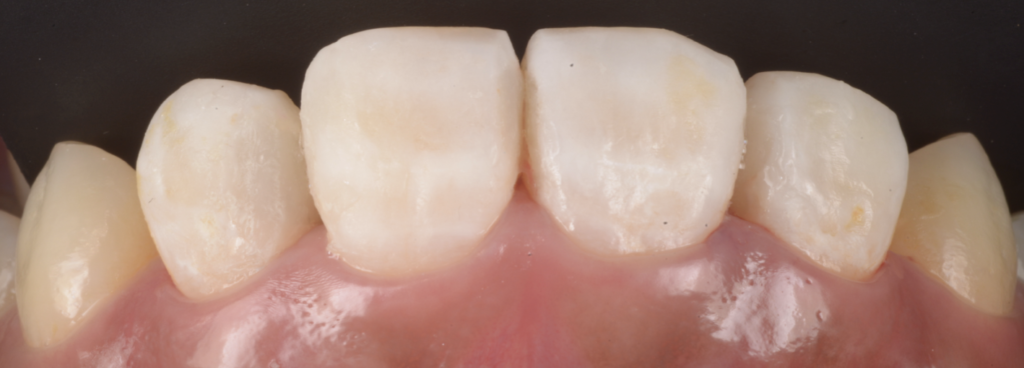

【今回の症例から】「詰めてあるのに、実は中で虫歯が進んでいた」

今回お伝えしたいのは、ここです。

患者さんは「詰め物が入っているから大丈夫」と思っていた。

見た目にも大きな痛みはない。

ただ、よく見ると着色が目立つ、そして詰め物が浮いているように見える。

そこで再治療のために詰め物を外してみると――

- 修復物の下で、虫歯が広がっていた

- 歯質が想像以上に脆く、削ると崩れる

- 結果として、当初の予想よりも歯の大半を失う形になってしまった

このケースは決して珍しくありません。

接着が破綻したところから微小漏洩が起き、そこに細菌が入り、見えない場所で増殖してしまう。

そして気づいた時には、表面の変色よりもずっと深部で病変が進行している――。